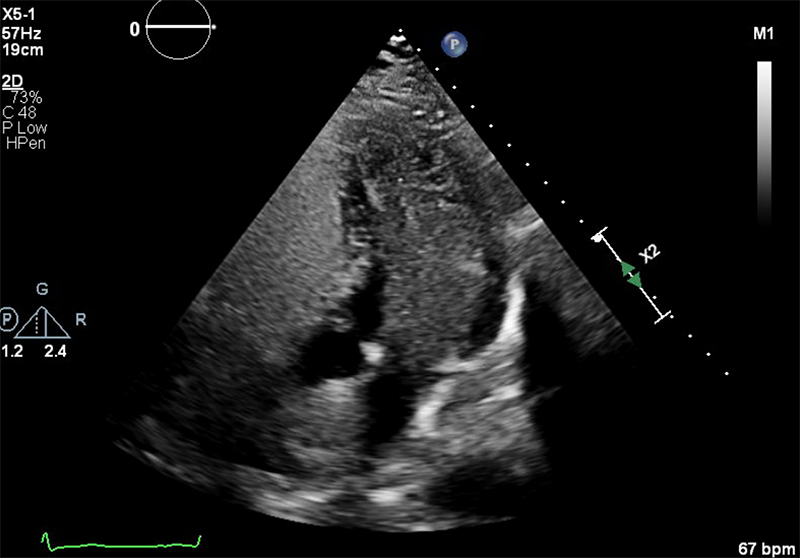

At this point, an intracardiac shunt was suspected and a bubble study with transthoracic echocardiography (TTE) was clearly positive with microbubbles almost completely filling the left heart chambers (figure 1). The dilated aortic root obscured the atrial septum so a PFO or ASD could not be identified. There was no evidence of a pulmonary arteriovenous malformation or hepatopulmonary shunt on CT scan. Transoesophageal echocardiography (TOE) with a bubble study confirmed a PFO measuring 40 mm maximally, causing a right-to-left shunt with large numbers of microbubbles crossing the interatrial septum when the patient was positioned at 45 degrees (semi upright) and less so when he was lying supine (figure 2).